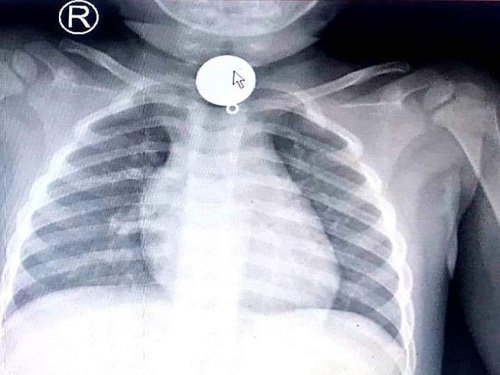

Bé trai 2 tuổi suýt mất mạng vì nuốt chửng mặt dây chuyền, lời cảnh tỉnh cho các bậc phụ huynh

Kết quả chụp X-quang, các bác sĩ phát hiện một dị vật mắc trong cổ bé rất to, chiếm hết lòng đầu trên thực quản,...